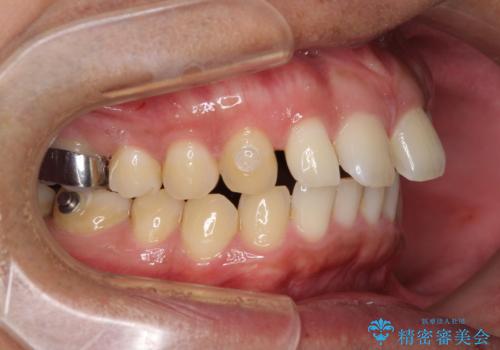

- 上顎前歯の突出感とすきっ歯を気にして来院された患者様です。

奥歯の咬み合わせを見ると、下顎に対して上顎が前方に位置していたため、補助装置により上顎歯列全体を後方に移動させ、その後インビザラインにて歯列全体を整えることとしました。